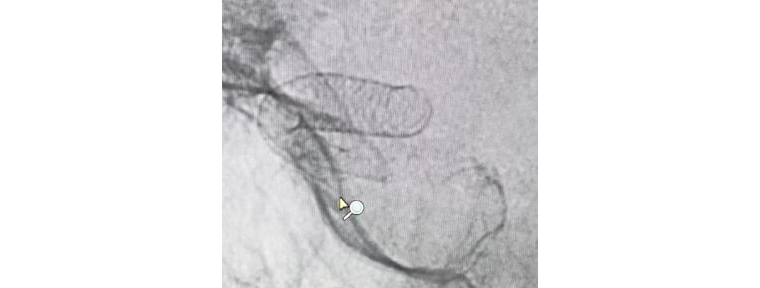

團(tuán)隊人員術(shù)前充分準(zhǔn)備,術(shù)中配合默契,支架順利釋放,造影觀察支架貼壁良好,瘤腔內(nèi)造影劑滯留,載瘤動脈通暢,手術(shù)非常成功。術(shù)后兩天,患者平穩(wěn)出院,對治療效果很滿意。

支架成功釋放